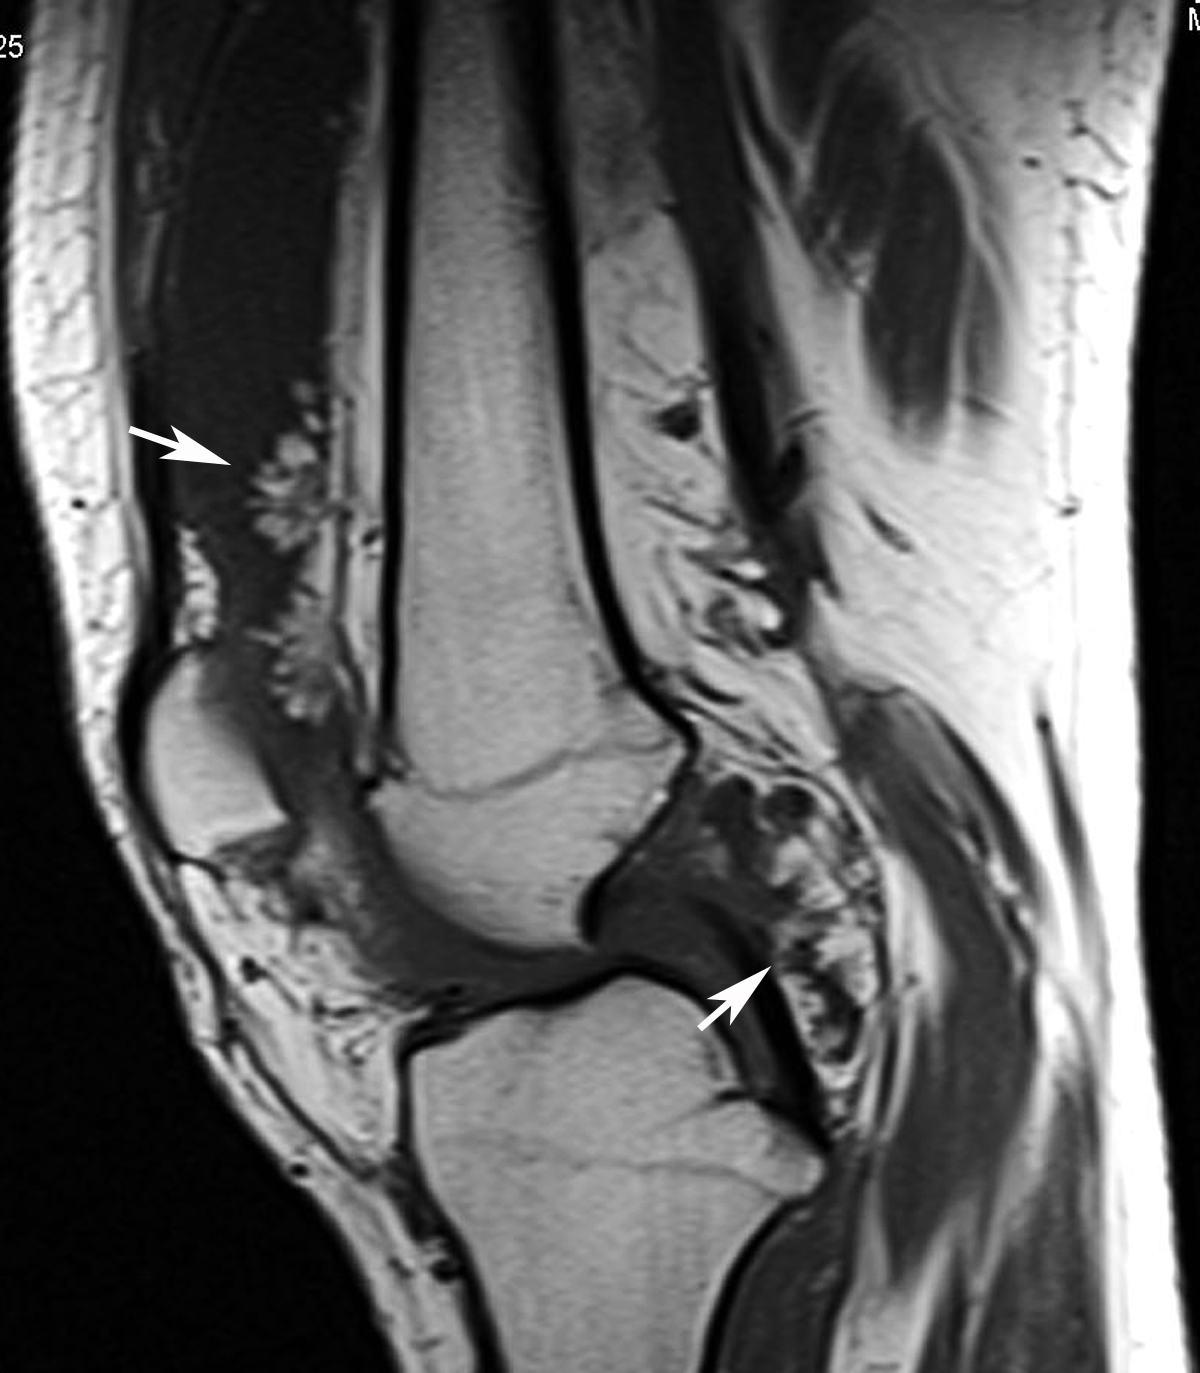

Preoprerative MRI. Magnetic resonance imaging of the right knee showed …

My Image 19